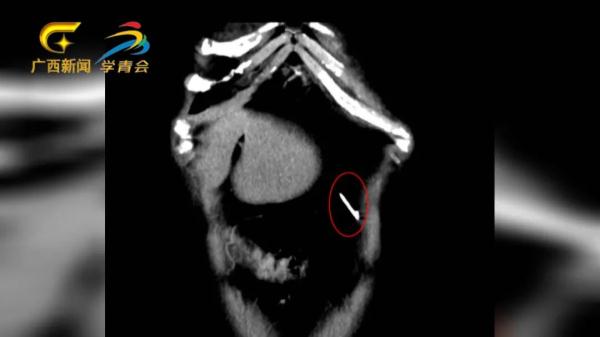

但是今年8月的一个早上,莫女士隐隐感觉左上腹部有些刺痛,尤其是弯腰活动时,刺痛感更加明显。她回想起当年的事,怀疑体内还有“漏网之针”,于是赶紧到附近的医院做了检查,果然在腹腔内发现了一枚针样金属影。但医生告诉她,由于异物太小,手术不一定能找到,且存在风险,建议到上级医院就诊。

经过一场“大海捞针”式的手术,医务人员从她的腹腔内“打捞”出这根缝衣针。剥去包裹的网膜组织,可以看到这枚钢针虽然锈迹斑斑,但仍然锋利无比。